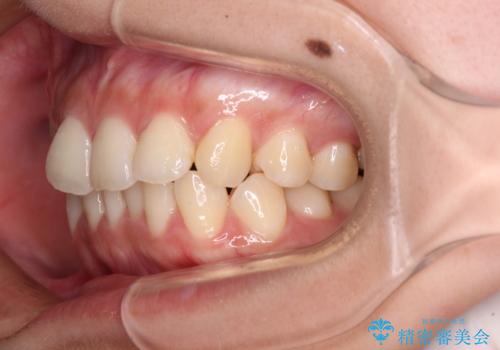

八重歯の抜歯矯正 補助装置とワイヤーを併用したインビザライン矯正治療

- 八重歯と上顎正中のズレを気にして来院された患者様です。

インビザラインによる矯正治療を希望されたため、八重歯改善のための抜歯矯正部分や上顎正中の大幅に位置移動は、補助装置やワイヤー矯正を併用し、その後はインビザラインにて行うこととしました。

骨格的に下顎が左側に変位していたため、上下正中を合わせることは困難であることは分かっていましたが、可能な限り合わせることができました。

骨格的なズレがあると仕上げの段階で奥歯の咬み合わせが不安定となるため、予定よりやや長期間となりました。